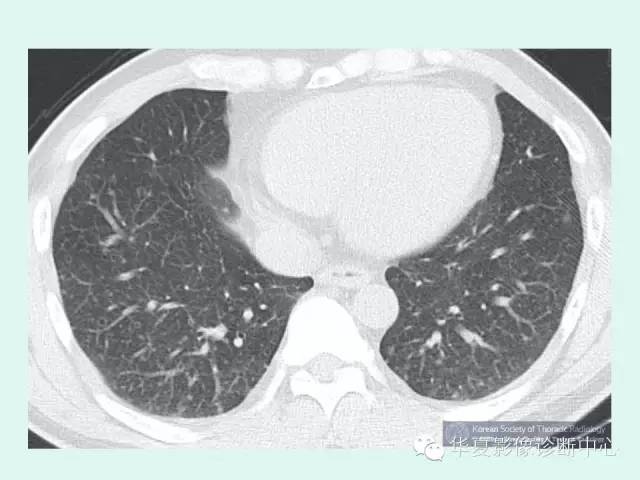

高分辨CT(HRCT)不仅对该病的鉴别诊断有意义,而且对判断该病的严重程度具有一定意义。病变通常分布在正常的肺组织中间,虽然在双下肺基底部位可以见到散在病变,但病变多位于上部,呈对称性均匀分布。早期病变主要以边界模糊的小结节阴影为主,有些病例可以见到有空洞形成。结节呈小叶中央性分布,并且伴有壁厚薄不等的囊性改变。随着病变的进展,囊性改变逐渐成为突出表现,这些囊腔大小差异很大,但通常直径小于1cm。囊腔可以为孤立样,也可互相融合,甚至形成肺气肿、气胸的表现。自发的出现小结节、空洞和囊性化是肺朗格汉斯组织细胞增生症较为特征性的改变。

3、晚期肺内纤维化 ,CT可表现为大小不等囊状影及纤维条索影,其囊状影形态呈圆形、类圆形,少部分囊状影亦可呈多边形、不规则形,囊壁薄而光整,囊壁<2mm,甚至部分囊壁在CT上观察不清,囊状影其直径一般<10mm以下,少数可大于10mm,可能与多个囊腔融合有关,随着囊状影的增多可出现蜂窝肺,此时可并发气胸,甚至反复出现,成为难治性气胸。

2、肺组织细胞增生症的囊样改变易于同特发性肺纤维化 的囊性病变相鉴别,后者的特征性表现是分布于胸膜下及基底部并伴有肺体积的减小。另外, PLCH的囊样变典型表现是囊样变为正常肺组织所包绕, 而特发性肺纤维化的蜂窝样囊性变伴有临近肺组织的异常, 诸如磨玻璃样变和结构紊乱。囊样变为主的PLCH还可以类似于淋巴管肌瘤病, 但是后者几乎只发生在女性并且弥漫地累及肺脏。PLCH的囊样病变类似于支气管扩张 , 但是这一疾病典型者缺少分枝表现。囊样变也可见于肺气肿 , 但是在这些病例中囊样变代表局灶性肺破坏, 缺少可见的壁。卡氏肺囊虫性肺炎 的患者可发展为肺囊肿或者肺气囊, 这将不容易同PLCH的囊样病变相鉴别。